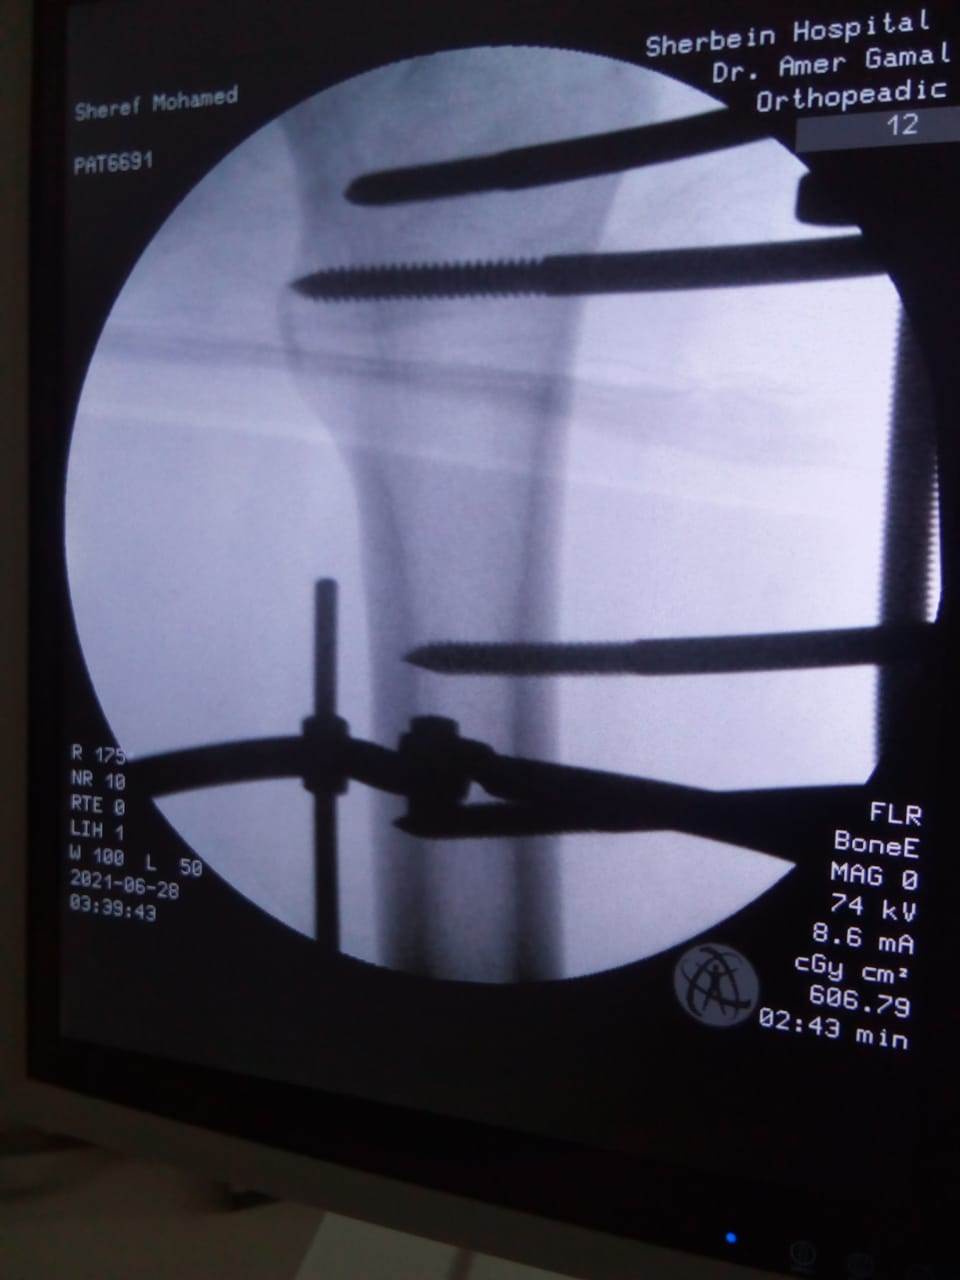

حيث تم إجراء تدخل جراحي دقيق لشاب يعاني من كسر مضاعف من الدرجة الثالثة، إثر طلق ناري، أدى إلى تهتك بالأنسجة، وكسور متفتتة بالفخذ، وذلك عن طريق جهاز "الليزاروف"، وتعد واحدة من عمليات العظام الكبرى والمتقدمة ذات المهارة الخاصة.